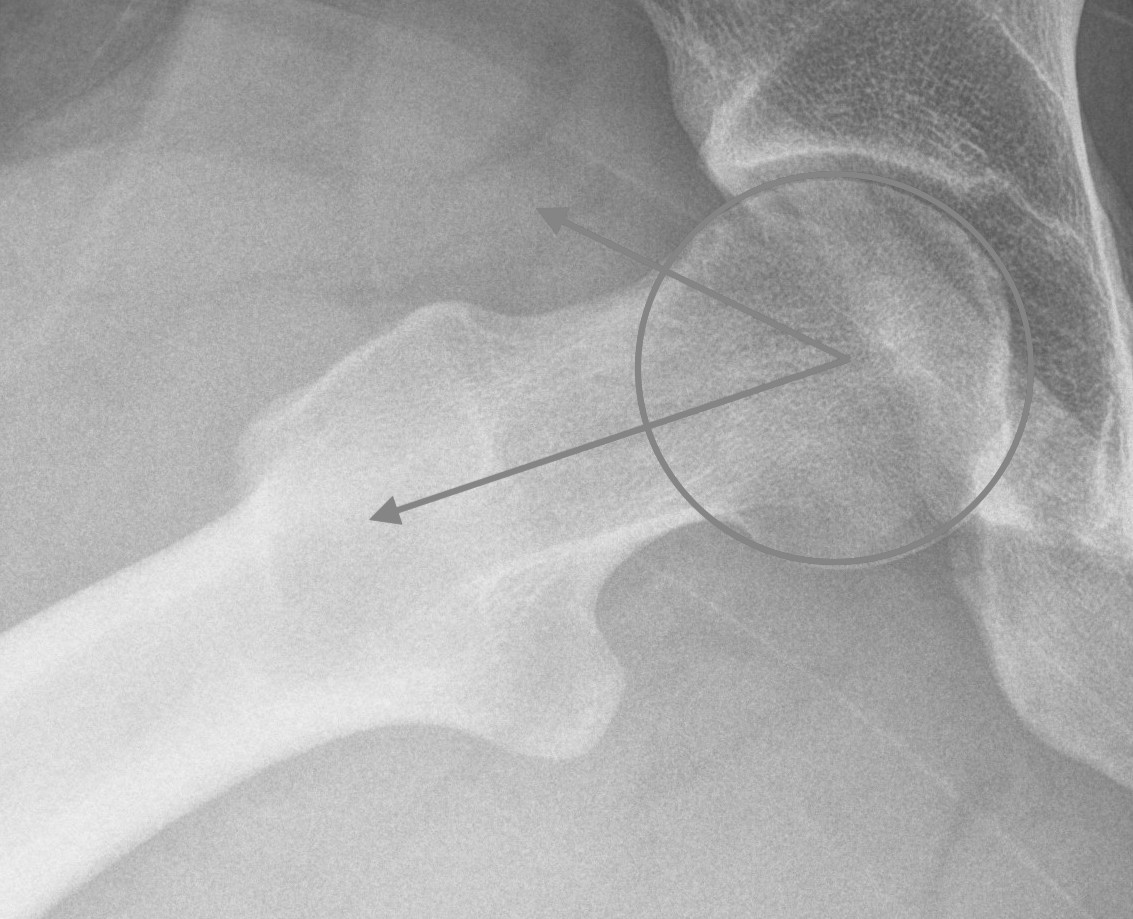

Alpha angle

Measurement

- centered in the center of the femoral head (best fit circle)

- formed by two lines

- one line center of the femoral neck axis

- a line where the femoral head leaves a best-fit circle

- higher alpha angle with Cam lesion

Alpha < 55 degrees Alpha > 55 degrees